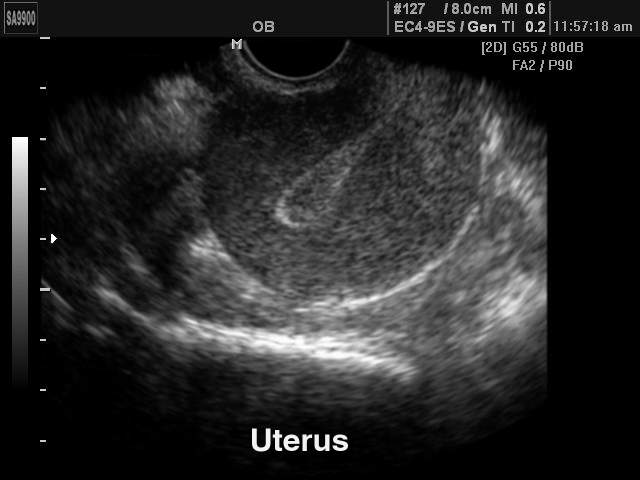

Трансвагинальная УЗИ-диагностика

Размеры матки в норме у женщин, расположение органа, толщину эндометрия и расположение яичников позволяет наиболее точно выявить трансвагинальная диагностика. Для этого датчик, который представляет собой пластиковый стержень 12 см в длину, вводится на небольшую глубину.

Процесс не доставляет неудобств, так как используется специальный гель, а диаметр устройства составляет всего 3 см. Из-за небольшой толщины стенок влагалища удается обнаружить любые, даже незначительные изменения. Благодаря этому, удается установить точный диагноз и подобрать своевременное лечение.

Узнать, в норме ли размеры матки у женщин можно благодаря трансвагинальному УЗИ.

Размер эндометрия

Эндометрий включает в себя два слоя – базальный и функциональный, которые чувствительны к воздействию гормонов. Функциональный слой отслаивается, что становится причиной менструаций. К концу месячных эндометрий становится тонким, а после овуляции его толщина оказывается максимальной. В этот период организм женщины готовится к беременности. Если она не наступает, цикл повторяется сначала.

Из-за такой особенности при обследовании учитывают фазу цикла:

- Начало цикла с выделениями. На 3-4 день цикла толщина эндометрия составляет 3-5 мм, происходит его постепенное восстановление.

- Пролиферация – средняя часть цикла. На 5-7 день цикла толщина составляет 6-9 мм, а уже к 10 дню достигает 1 см. На 2 неделе параметры могут достигать 1, 3 см.

- Секреция – завершение цикла. К 18 дню цикла толщина достигает 1-1,6 см, а к 20-23 дню параметры оказываются максимальными – 1-2,1 см. Затем происходит постепенное уменьшение размеров до 1- 1,8 см.